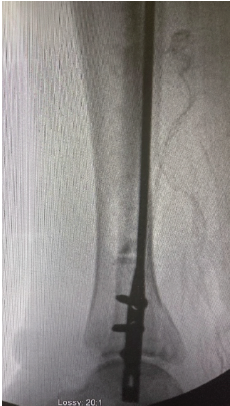

Baastrup’s Disease, a Rare Cause of Cauda Equina Syndrome: Case Report

Aniruddha Vaidya , Sushil Mankar , Nitin Pothare , Vismay Harkare

………………………………p.63-67